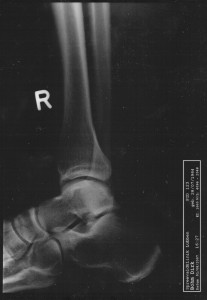

... jedoch wir kamen dort zu ganz überraschenden Urlaubsfotos. Kurz nach unserer

Ankunft begann mein rechter Knöchel ohne ersichtlichen Grund kontinuierlich anzuschwellen. Nach 1 1/2 Tagen war der Gang in die Notaufnahme unvermeidlich - und da entstanden die prächtigen Fotos.